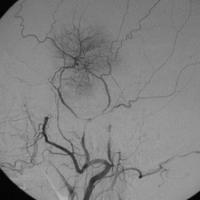

1、腦血管造影間接型頸動脈海綿竇瘺腦血管造影檢查的目的是確定瘺口的位置,供血動脈,靜脈引流形式,有無頸外動脈系統與頸內動脈系統和椎動脈系統的“危險吻合”等。腦血管造影檢查的內容包括患側頸內動脈的選擇造影,患側的椎動脈,頜內動脈,咽升動脈造影和對側頸內動脈和頸外動脈的選擇造影。微導管超選擇造影可進一步了解各供血動脈的供血情況。正常情況下,海綿竇接受眼上、下靜脈和蝶頂竇的引流,再經岩上、下竇引流到橫-乙狀竇交界處和頸靜脈球。兩側的海綿竇經海綿間竇相交通。在CCF存在的情況下,海綿竇內壓力增高,血流方向發生改變:經眼上靜脈逆流入角靜脈和面靜脈,經海綿間竇注入對側海綿竇,以及逆流入蝶頂竇等。此類頸動脈海綿竇瘺的供血情況通常非常複雜。在經動脈途徑栓塞治療前,必須仔細研究腦血管造影,特別注意有無“危險吻合”的存在。頸總動脈分叉處的情況也是腦血管造影要觀察的重要內容。如果該處有動脈粥樣硬化斑塊,則禁止採用壓迫頸總動脈的方法治療間接型頸動脈海綿竇瘺。